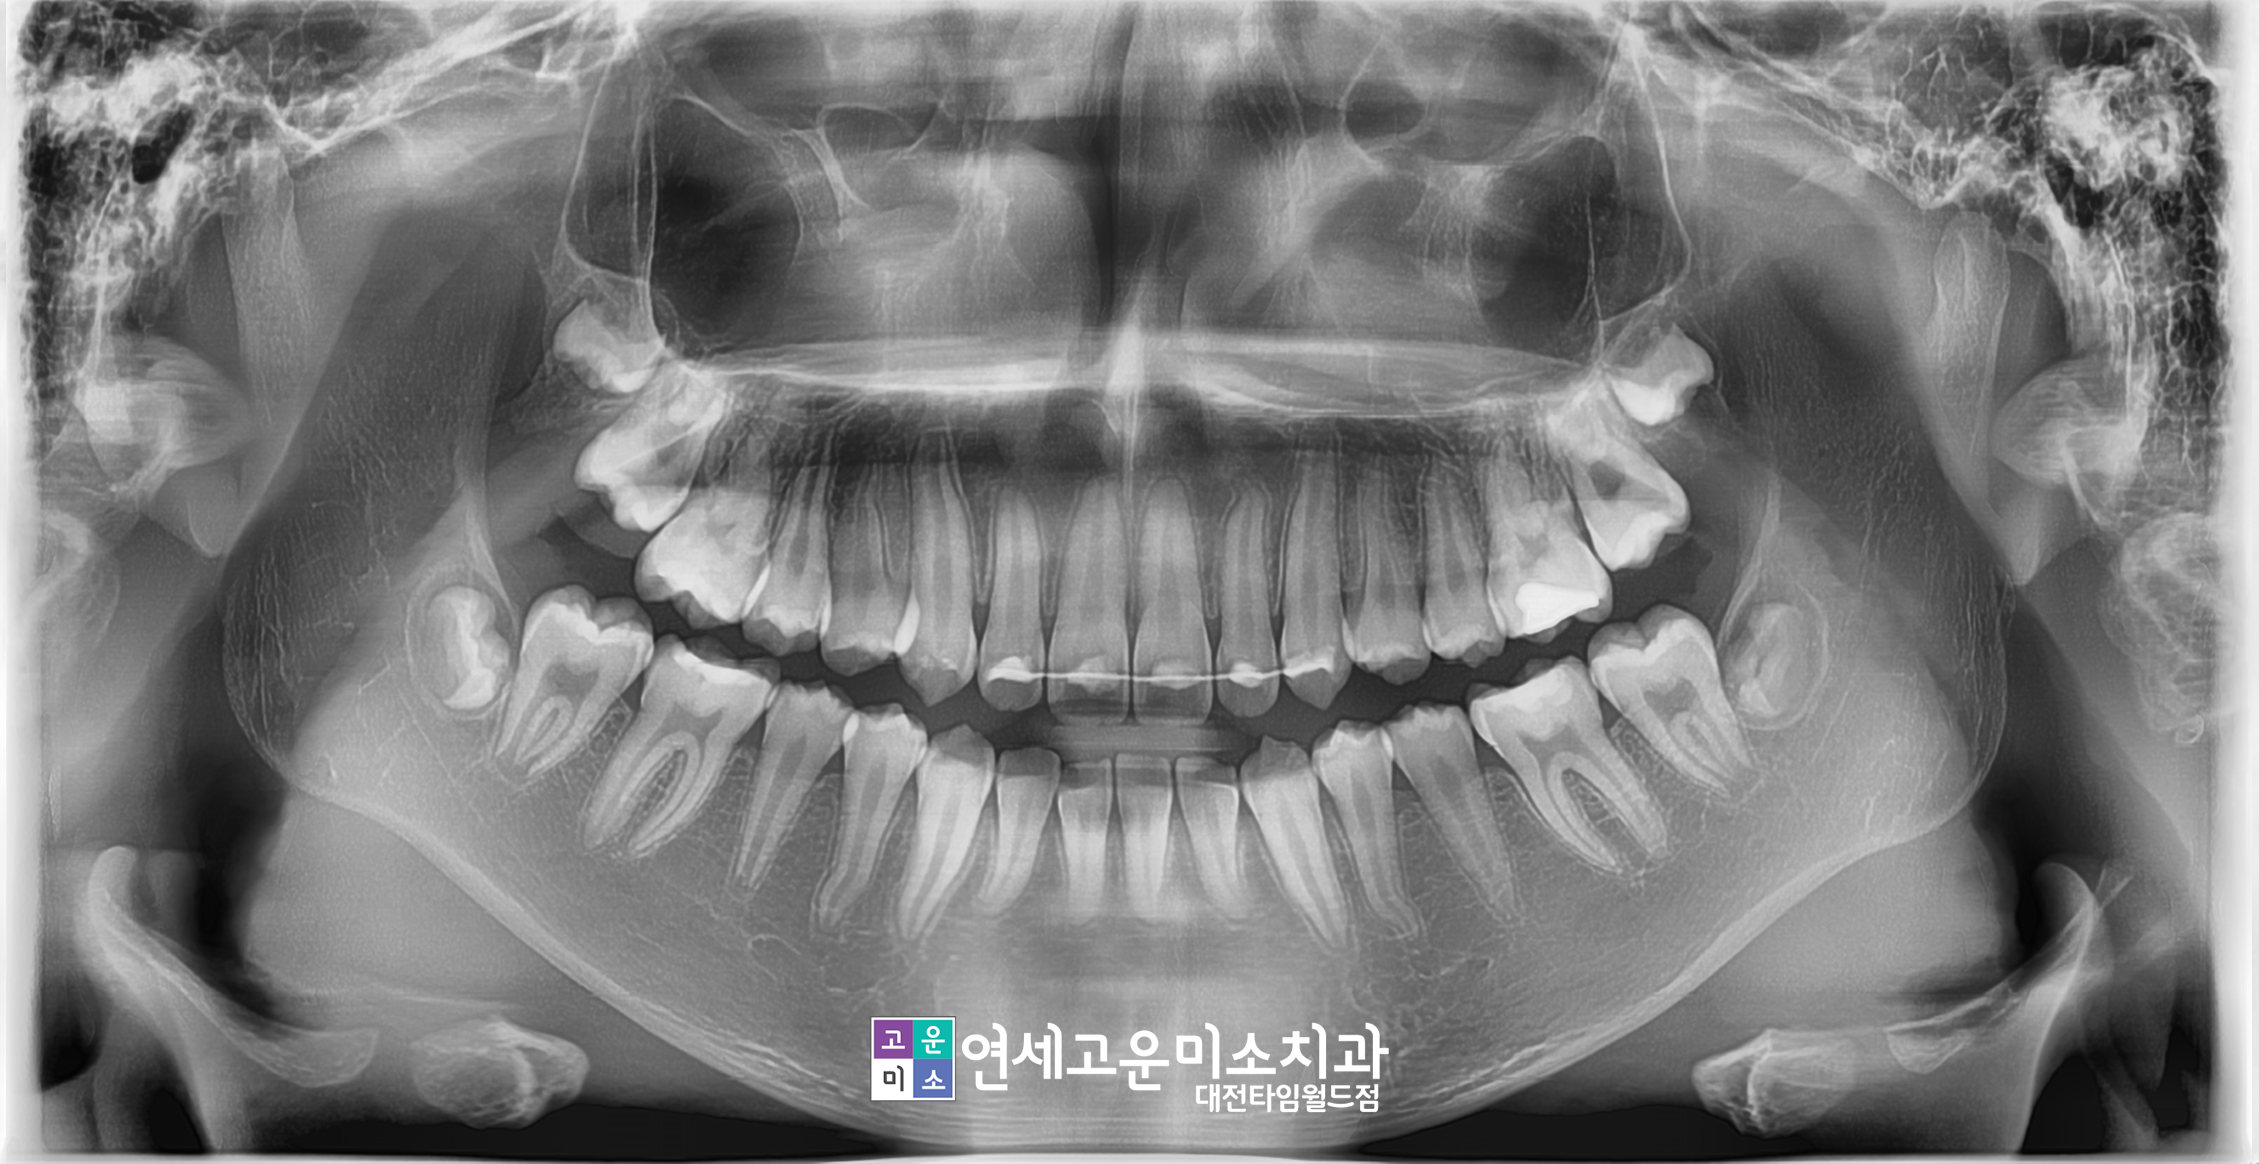

치료 완료 후 모습입니다.

치아는 하나도 빼지 않고 교정이 완료되었으며

모든 영구치가 제자리에 잘 자리 잡았습니다.

물론 치료 기간은 3년 조금 넘게 진행하였지만

보호자분도 의료진도 모두 만족한 상태로 마무리가

되었습니다.

조기에 영구치 맹출을 잡아주었기 때문에

발치를 하지 않아도 되는 케이스에서 발치하지 않고

마무리할 수 있었던 것 같습니다.